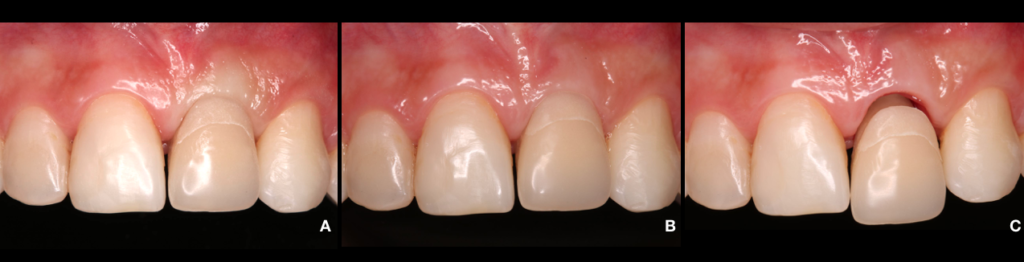

Utilizamos inicialmente um pilar de titânio anti-rotacional (AR) provisório para a captura do dente que estava na contenção estética removível. Assim, delimitamos todos os contornos e subcontornos das áreas críticas e subcríticas favorecendo a migração coronal da gengiva, resultando em uma melhor condição estética na posição da margem cervical do tecido mole (Frizzera, 2018). Fig.6A/B/C

Ao instalar o provisório, ainda pudemos melhorar a arquitetura do tecido em relação aos tecidos adjacentes utilizando um método clínico que é a técnica de compressão dinâmica, o objetivo desta técnica é estabelecer um perfil de emergência adequado, nivelar o contorno da margem gengival, zênite, largura da papila e a forma triangular do perfil e estabelecer um ponto de contato (Wittneben, 2013). Fig.7A/B/C